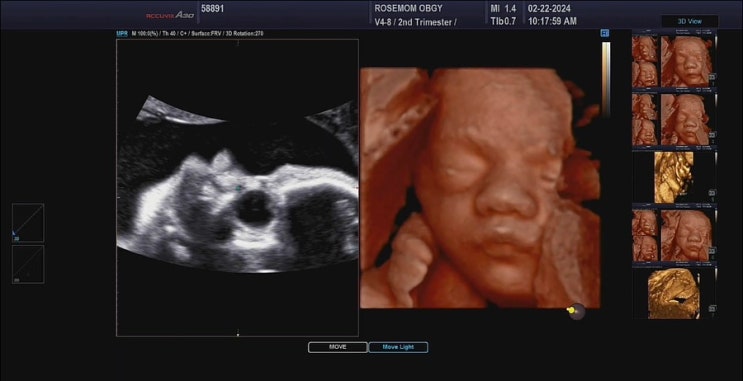

대구 로즈맘산부인과 입체초음파 후기 28주

저는 첫째때는 친정인 광주 W여성병원에서 출산을 했어요 그때 진료받을때마다 초반에는 4주에 한 번씩 후...